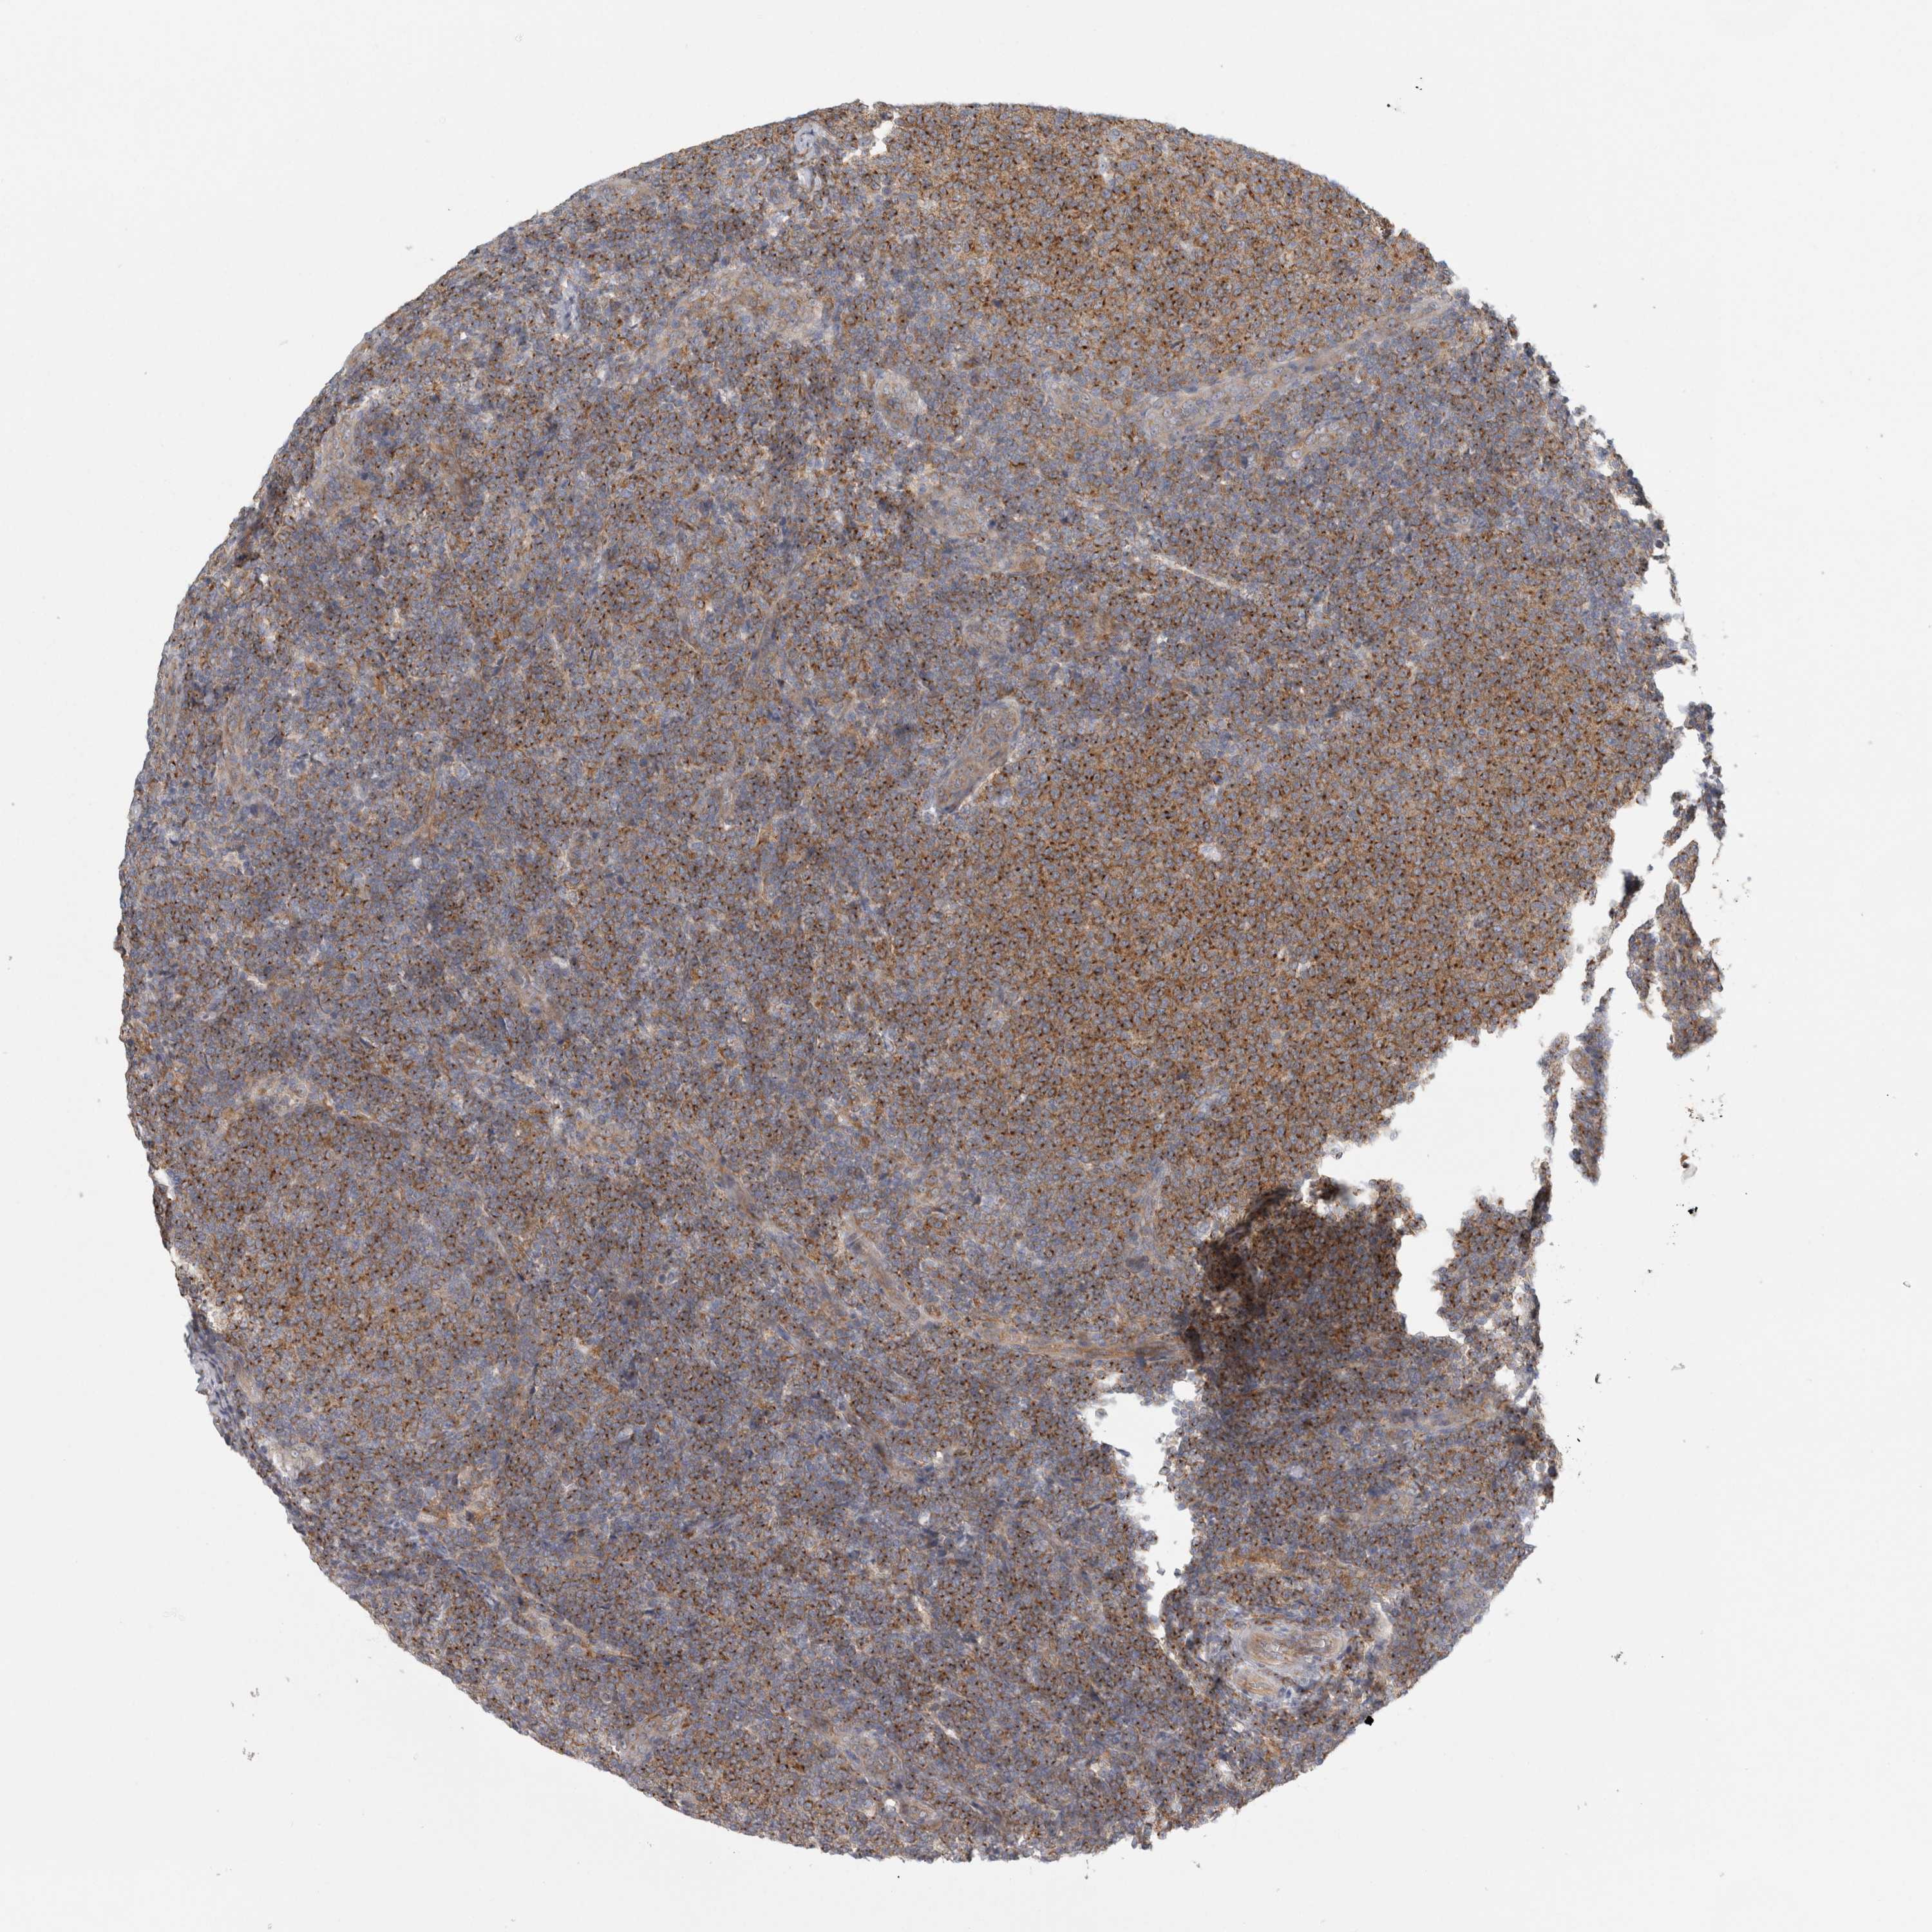

LYMPHOMA - Protein expressioni

A mouse-over function shows sample information and annotation data. Click on an image to view it in a full screen mode. Samples can be filtered based on level of antibody staining by selecting one or several of the following categories: high, medium, low and not detected. The assay and annotation is described here.

Antibody stainingi

Antibody staining in the annotated cell types in the current human tissue is reported as not detected, low, medium, or high, based on conventional immunohistochemistry profiling in selected tissues. This score is based on the combination of the staining intensity and fraction of stained cells.

Each image is clickable and will lead to virtual microscopy that enables deeper exploration of all samples and also displays staining intensity scores, fraction scores and subcellular localization as well as patient and tissue information for each sample.

Antibody HPA025924

Staining

High

Medium

Low

Not detected

Intensity

Strong

Moderate

Weak

Negative

Quantity

>75%

75%-25%

<25%

None

Location

Nuclear

Cytoplasmic/membranous

Cytoplasmic/membranous,nuclear

Hodgkin's disease, NOS

Malignant lymphoma, non-Hodgkin's type, High grade

Malignant lymphoma, non-Hodgkin's type, Low grade